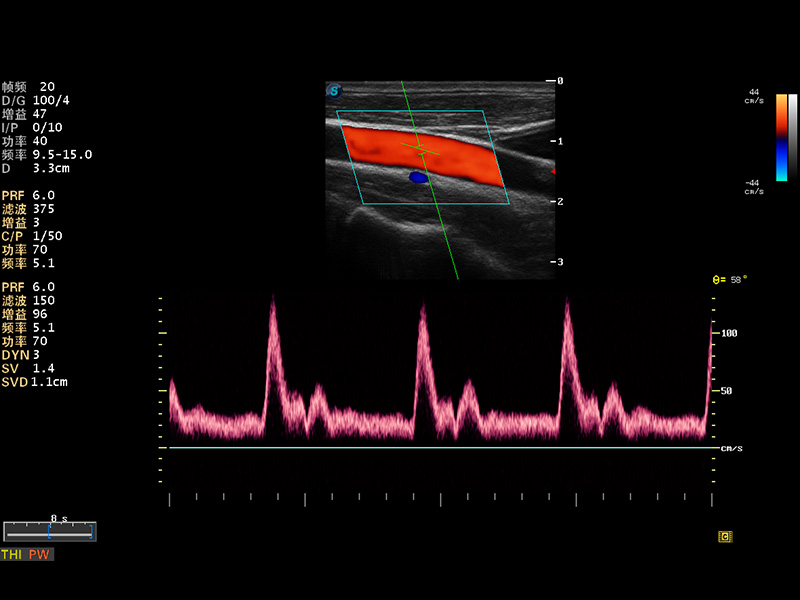

S8 EXP便携式彩色多普勒超声诊断仪是云顶集团官网研发的高端全身应用型便携彩超。高通道的VIS平台融合可视化(Visual)、智能化(Intelligent)和人性化(Smart)的特点,配以云顶集团官网自主研发生产的探头大家族,使您能够快速、准确的获得病人信息,提高工作效率的同时减轻疲劳。

多波束形成器

μ-Scan微米成像